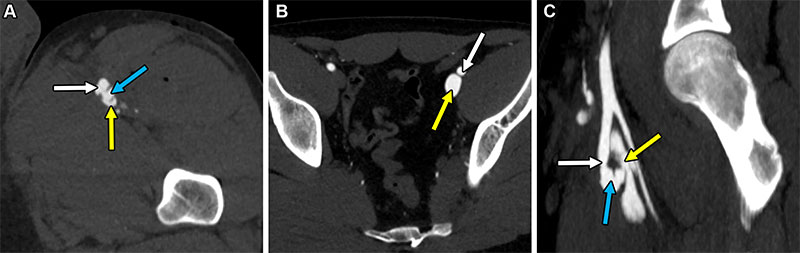

Arteriovenous fistula resulting from a gunshot injury in a 27-year-old man. (A) Axial arterial phase CT image shows an irregularly shaped channel (blue arrow) between the left superficial femoral artery (white arrow) and corresponding vein (yellow arrow). (B) Axial arterial phase CT image shows abnormal asymmetric early enhancement of the left external iliac vein (yellow arrow) similar to the degree of enhancement of the left external iliac artery (white arrow), upstream from the AVF. (C) Oblique sagittal arterial phase MIP CT image shows the fistula (blue arrow) between the superficial femoral artery (white arrow) and corresponding vein (yellow arrow).

https://doi.org/10.1148/rg.240272 © RSNA 2025